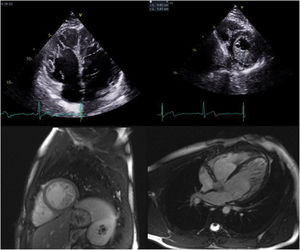

The family pedigree (Figure 2) revealed that both the patient's parents were already deceased, the father from dementia and the mother from cancer. The patient had nine siblings, including one sister who died in childhood of unknown cardiac disease and one brother who died in infancy of unknown cause. Two other brothers were deceased, one from pneumonia in infancy and one from cancer at 27 years of age. Her 49-year-old brother underwent transthoracic echocardiography, which was normal. Her 47- and 41-year-old sisters also underwent echocardiographic screening (Figure 3) and both exams resulted in a diagnosis of LVNC (Table 2). They also underwent MRI which corroborated these findings (Figure 3). The 41-year-old sister has an eight-year-old son who was also diagnosed with LVNC by echocardiographic screening. Her 28-year-old daughter has a normal echocardiogram and her 22-year-old son had pronounced LVNC with right ventricular involvement on the echocardiogram as well as on cardiac MRI (Figure 4). He also received an ICD due to non-sustained VT.

| Son, 22 years | PalpitationsNon-sustained VT | Normal LV functionHypertrabeculated myocardium meeting the Chin, Jenni and Stöllberger criteria of LVNC | Petersen criteria of LVNC (ratio of thickness of noncompacted/compacted layers reported as >2.3)LVEF: 53%No late enhancement |

Transthoracic echocardiogram in 4-chamber view of the index patient's son showing biventricular involvement (top left) and a ratio of thickness of noncompacted to compacted layers >2, clearly fulfilling the diagnostic criteria of Jenni et al. for left ventricular noncompaction (LVNC) (top right); cardiac magnetic resonance images in short-axis view of the same patient showing hypertrabeculation (bottom left) and ratio of the thickness of noncompacted to compacted layers >2.3 in 4-chamber view, fulfilling Petersen et al.’s criteria of LVNC (bottom right).